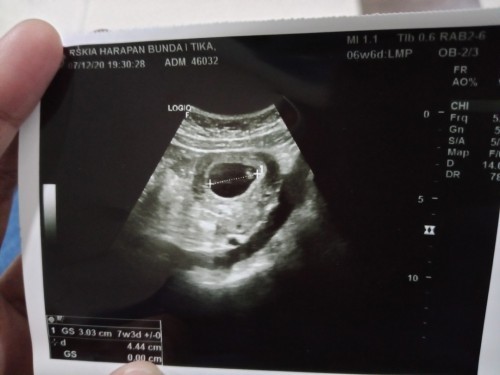

Bunda , #seriusnanya #bantusharing saya hamil 33 minggu , ketuban saya kata dokter sedikit bgt pdhl minum byk , trs kata dokter plasenta saya jelek , berat badan si dedek hanya 2kg . ada yg sama kaya saya ga bunda 😭😭😭 pliss bantu jawab bunda . saya panik soalnya ini anak pertama !! Gimana caranya agar plasenta bagus ,dan ketuban kembali penuh ,, trs apa normal si dedek 33 minggu bb nya 2kg . #seriusnanya #bantusharing #pleasehelp #firstbaby 😭😭😭😭